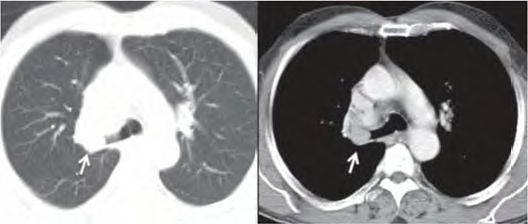

Uma paciente de 47 anos de idade, não tabagista, apresenta episódio de tosse e hemoptise. A tomografia computadorizada de tórax, realizada para investigação, evidenciou um nódulo pulmonar, com densidade de partes moles, de 2,1 cm, com obstrução do brônquio lobar superior direito, demonstrada nas imagens a seguir. Não há linfonodos mediastinais aumentados. A fibrobroncoscopia para investigação evidenciou uma lesão sólida em brônquio lobar superior direito, com obstrução total do brônquio, e aspecto em “dedo de luva”. As tomografias computadorizadas de abdome e de crânio não identificaram lesões metastáticas a distância. A biópsia endobrônquica demonstrou ser um carcinoide típico.

A espirometria permite ressecção pulmonar (lobectomia e pneumonectomia), e a avaliação clínica pré-operatória permite cirurgia de grande porte.

Acervo Pessoal.